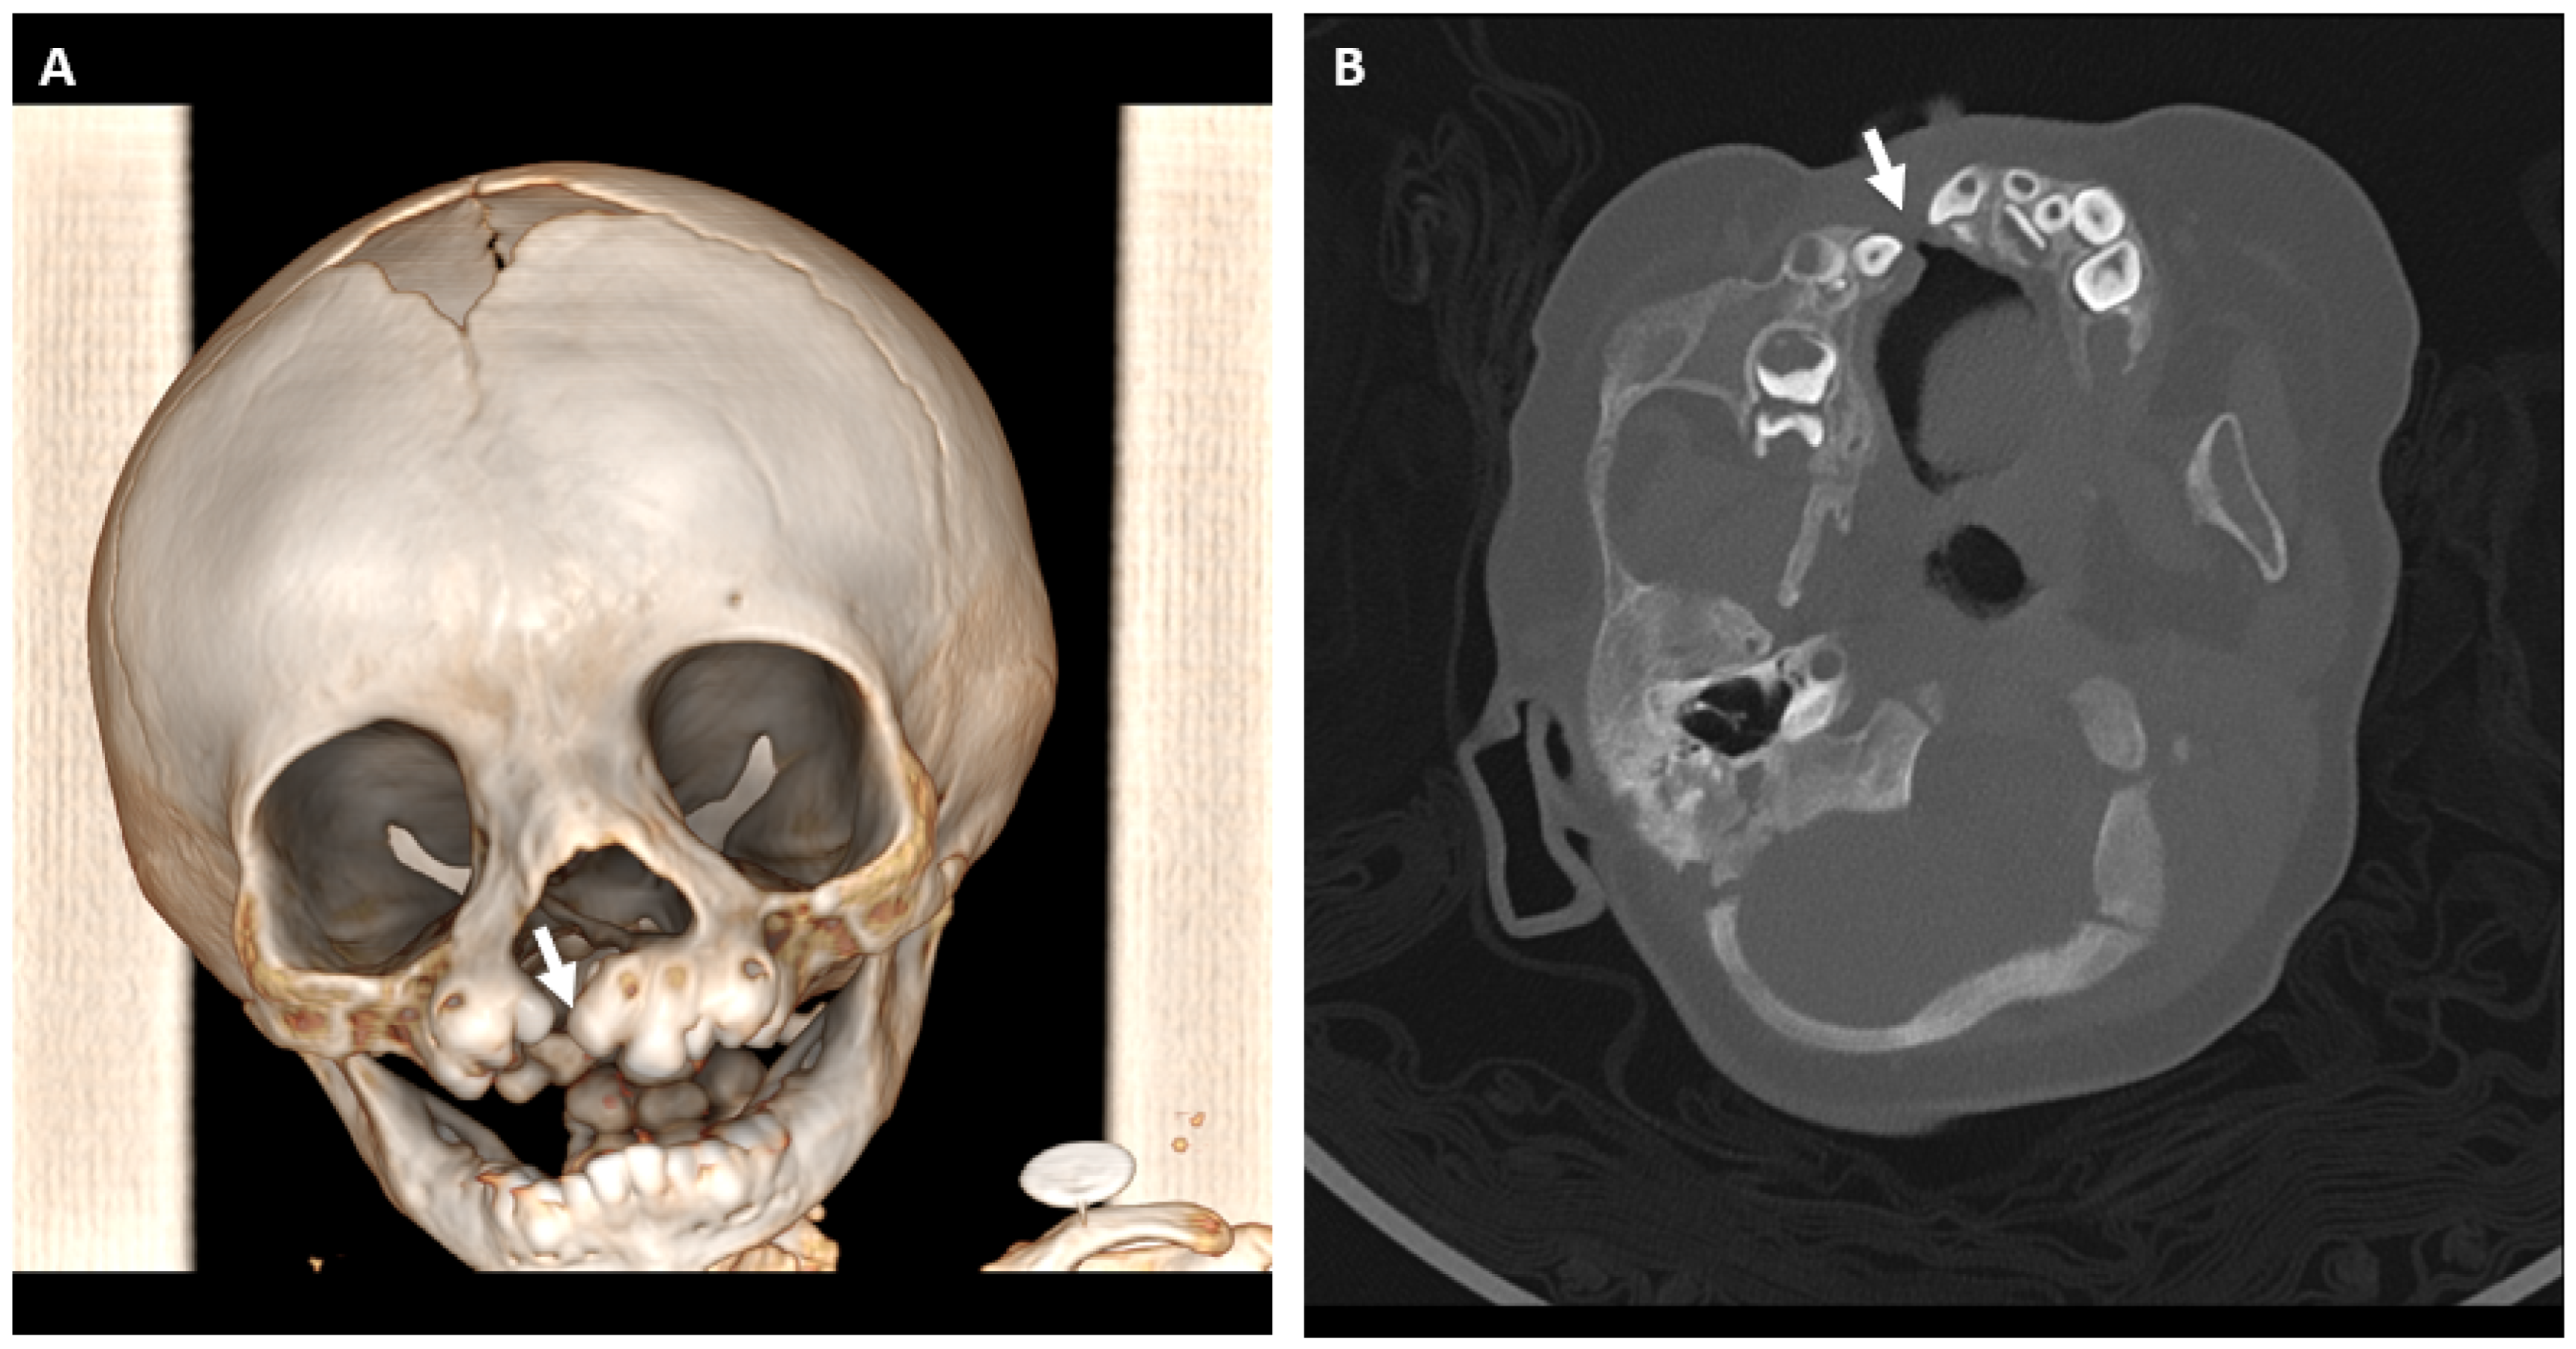

3.5. Anatomical and Imaging Correlations to Odontogenic Infectious Disease

3.5.2. Dental Decay Radiologic Correlations